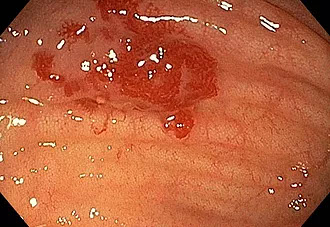

Angiodiplasias

Es la presencia de vasos sanguíneos inflamados y frágiles en el colon. Esto puede resultar en una hemorragia desde el tracto gastrointestinal (GI).

La angiodisplasia del colon está en gran parte relacionada con el envejecimiento y la descomposición de los vasos sanguíneos. Por lo general, ocurre en adultos mayores y casi siempre se ve en el lado derecho del colon.